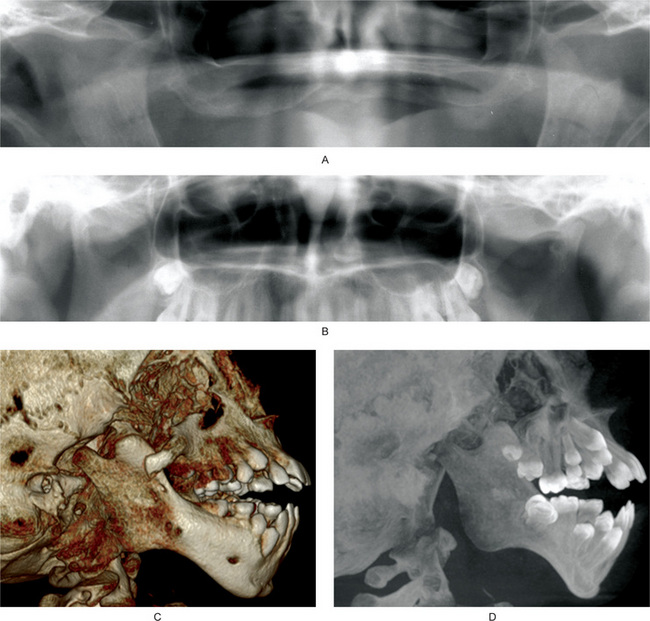

Condylar aplasia is failure of development of the mandibular condyle, while condylar hypoplasia is underdevelopment of the condyle. Aplasia or hypoplasia may be congenital or acquired, and may occur unilaterally or bilaterally (Fig 17-36A, B).

Figure 17-36 Developmental disturbances of temporomandibular joints.

Aplasia and hypoplasia of the TMJ. (A) Cropped panoramic radiograph showing bilateral aplasia of the TMJs. The finding is worse on the left side. The coronoid processes appear hyperplastic. (B) Cropped panoramic radiograph showing hypoplasia of the right condylar head. Compared to the left condylar head, the anteroposterior dimension of the right condylar head is small. The left condylar head has flattening of the lateral surface, consistent with degenerative joint disease. (C) Treacher Collins syndrome, 3-D reconstruction of a cone beam computed tomography data. (D) Same patient as in Figure C. Maximum intensity projection of cone beam computed tomography data. Figures C and D showing hypoplastic condylar head and coronoid process. Zygomatic arch is partially formed. Anterior teeth are protruded. Antegonial notch is prominent. In Treacher Collins syndrome, hypoplasia of the condylar heads is bilateral.

Congenital or primary hypoplasia or aplasia is characterized by unilateral or bilateral underdevelopment of the condyle, usually due to disturbances in the first or second branchial arches. Conditions that show congenital hypoplasia or aplasia include Treacher Collins syndrome (Fig. 17-36C, D), oculo-auriculo-vertebral syndrome, hemifacial macrosomia, Pierre Robin sequence, and Hurler syndrome. In congenital variety, both the joints are usually affected but the primary clinical findings may be unilateral.

Condylar hyperplasia is a rare unilateral enlargement of the condyle (Fig. 17-37A,B, C) which should not be confused with a neoplasm of this structure, although it may superficially resemble an osteoma or chondroma. The cause of this condition is obscure, but it has been suggested that mild chronic inflammation, resulting in a condition analogous to a proliferative osteomyelitis, stimulates the growth of the condyle or adjacent tissues. The unilateral occurrence strongly suggests a local phenomenon. Obewegeser and Makek have classified condylar hyperplasia into three categories. Type A is hemimandibular hyperplasia, causing asymmetry in the vertical plane. In this type, the growth is unilateral in the vertical plane, with minimal deviation of the chin. Typically, maxilla shows compensatory growth. In absence of the maxillary growth, an open bite may be present on the same side. Type B is hemimandibular elongation, causing asymmetry in the transverse plane. In this type, the chin is deviated towards the contralateral side with no vertical asymmetry. Patient may exhibit cross-bite. Type C is a combination of type A and type B, and exhibits hyperplastic features unilaterally or bilaterally.

Figure 17-37 Developmental disturbances of temporomandibular joints.

Figures (A and B) are from the same patient. Three-dimensional reconstruction of a computed tomography data. The left condylar head is hyperplastic. Please note that left condylar head is too large for the articular fossa, and is permanently dislocated anterior to the articular eminence. (C) Cropped panoramic radiograph shows hyperplasia of the left condylar head. (D) Axially corrected coronal views of the temporomandibular joints from four different patients from cone beam computed tomography scans. Bifid condyles may have slight midline depression to almost a duplication of the condylar head.

Condylar hyperplasia occurs more frequently in females. Patients of any age may be affected, although most common occurrence is in the third decade of life. Diagnosis of condylar hyperplasia is made by a combination of clinical and radiographic findings. The patients usually exhibit a unilateral, slowly progressive elongation of the face with deviation of the chin away from the affected side. The enlarged condyle may be clinically evident or at least palpated and presents a striking radiographic appearance in both coronal and sagittal views. The affected joint may or may not be painful. A malocclusion is a usual sequel of the condition.

Bifid condyle is characterized by a varying depth of groove or depression around the midline of the condylar head (Fig. 17-37D). The depression may be visible on coronal or sagittal orientation. A deep groove may result into an appearance of duplicity of the condylar head. Usually, bifidity is unilateral, although bilateral bifid condyles have been reported. Bifidity is a rare condition, effecting less than 1% of the population. Even rarer are trifid condyles. The etiology of bifidity is controversial. Two etiologies of bifid condyles have been suggested. One theory speculates that bifidity may originate in embryo where blood supply to the condylar head is limited. Another theory suggests trauma being the cause of bifidity, either due to birth trauma or fracture of the condylar head. Usually patients with bifid condyles are asymptomatic and do not require any treatment. Relationship of bifid condyles to articular disks is not clearly known.